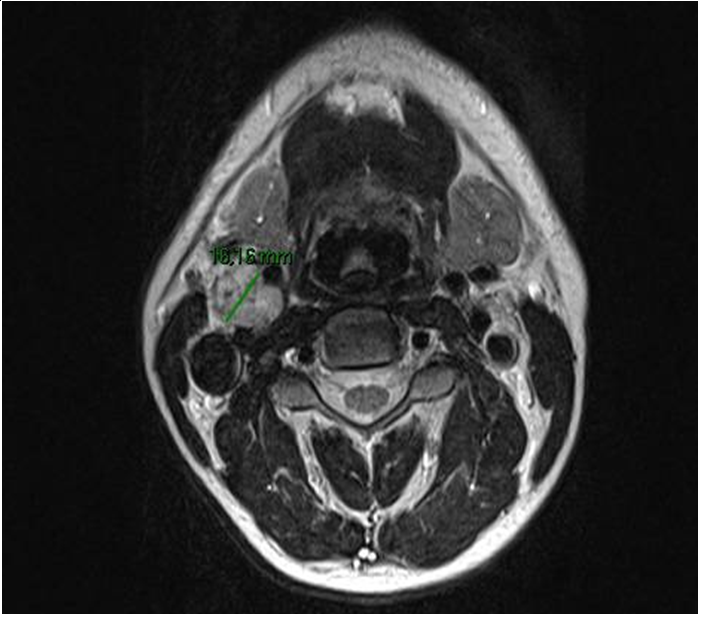

A 31-years old caucasian man came to the neurology emergency department because of the sudden onset of right-sided palsy with sluttered speech. He reported no headache, dizziness or convulsions. After the initial workup, he was admitted to the neurology department. MRI showed subacute ischemic stroke in the posterior part od left insula and operculum. 3D- TOF MR angiography showed occlusion of one of the smaller branches in M2/M3 segment. We performed a doppler ultrasound of carotid and vertebral arteries that indicated vascularized parenchymal structure between ACI and ACE on the right side (Figure 1). Because of that, we did MRI of the neck that verified the inhomogenic structure at the bifurcation of carotid arteries od the right side, dimensions 2,6X1,8X1,9cm that resembles paraganglioma (Figure 2).

Figure 2 MRI of the patients neck showing large paraganglioma between internal and external carotid arteries.